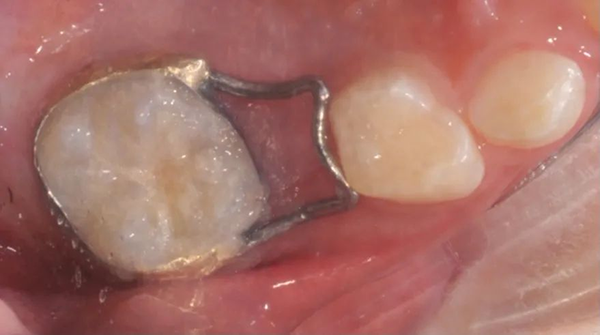

临床上用的比较多的是丝圈式的间隙保持器(见下图),这种保持器适合单颗乳磨牙缺失的情况。

间隙保持器